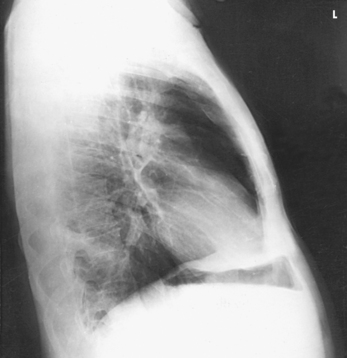

Structures shown: The preliminary left lateral chest position is used to show the heart, the aorta, and left-sided pulmonary lesions (Figs. 10-37 and 10-38). The right lateral chest position is used to show right-sided pulmonary lesions (Fig. 10-39). These lateral projections are employed extensively to show the interlobar fissures, to differentiate the lobes, and to localize pulmonary lesions.

Fig. 10-38 A, Left lateral chest. B, Right lateral chest on same patient as in A. Note the size of the heart shadows.